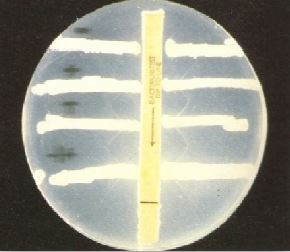

محامي وصل منذ ثلاثة أيام من السفر أحضر إلى قسم الطوارئ وهو يعاني من تقرح الحلق sore throat و orodynia ، صداع مع فشل عام، كما يعاني من ارتفاع في درجة الحرارة ونوبات تسرع ضربات القلم tachycardia . بفحص البلعوم لوحظ وجود غشاء ملتصق على الحلقوم. اخذت مسحة وأرسلت إلى مختبر التحليل الجرثومي لفحصها مجهرياً كما في الشكل رقم 1 وزراعتها على وسط غذائي مناسب كما في الشكل رقم 2 . تم إجراء الاختبار المعملي كما في الشكل رقم 3 .

الشكل رقم 3 الاختبار المعملي

2- كيف يتم التأكد من هذا التشخيص معملياً ؟ وما اسم الاختبار الموجود في الشكل رقم 3 ؟

وكذلك الوسط الغذائي المغذي Loeffler's agar المائل ويتم التعرف على البكتيريا المعزولة بإجراء الاختبارات الكيموحيوية ويكشف على الذيفان بطريقة Elek's كما في الشكل رقم 3 ، حيث يجري هذا الاختبار بغمر ورقة الترشيح في مضاد الذيفان ثم وضعها على الطبق المحتوي على الوسط الغذائي المناسب ، بعد ذلك تزرع البكتيريا قيد الاختبار على الطبق مع زرع بكتيريا سالبة وأخرى موجبة لهذا الاختبار على الطبق مع زرع بكتيريا سالبة وأخرى موجبة لهذا الاختبار للتأكد من صحة النتائج المتحصل عليها، إلا أنه من الأفضل استعمال تقنية التفاعل التسلسلي للبوليمرات (PCR) للكشف عن السلالات المنتجة للذيفان.